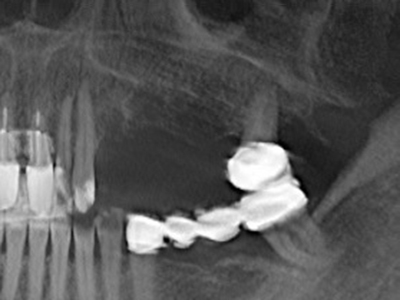

Quando le procedure chirurgiche vengono eseguite sull'osso nelle immediate vicinanze di strutture sensibili, come vasi sanguigni o nervi, gli strumenti rotanti pongono un rischio significativo di lesione iatrogena. I dispositivi piezoelettrici possono essere utili per la preparazione delle coperture ossee e la rimozione del tessuto duro in prossimità dei nervi, in particolare per la loro esposizione dopo una lesione iatrogena, ma anche durante la lateralizzazione dei nervi per le procedure di resezione e ricostruzione o il posizionamento di impianti (figg. 17-20). Il contatto leggero tra puntina piezoelettrica e nervo non causa generalmente danni, ma se si procede senza prestare attenzione con movimenti a sega o raccordi con residui di substrati ossei possono verificarsi danni al nervo temporanei o anche permanenti. Il rischio di danno, tuttavia, è considerato sostanzialmente inferiore al rischio presente utilizzando seghe o frese (Pereira, Gealh et al. 2014).